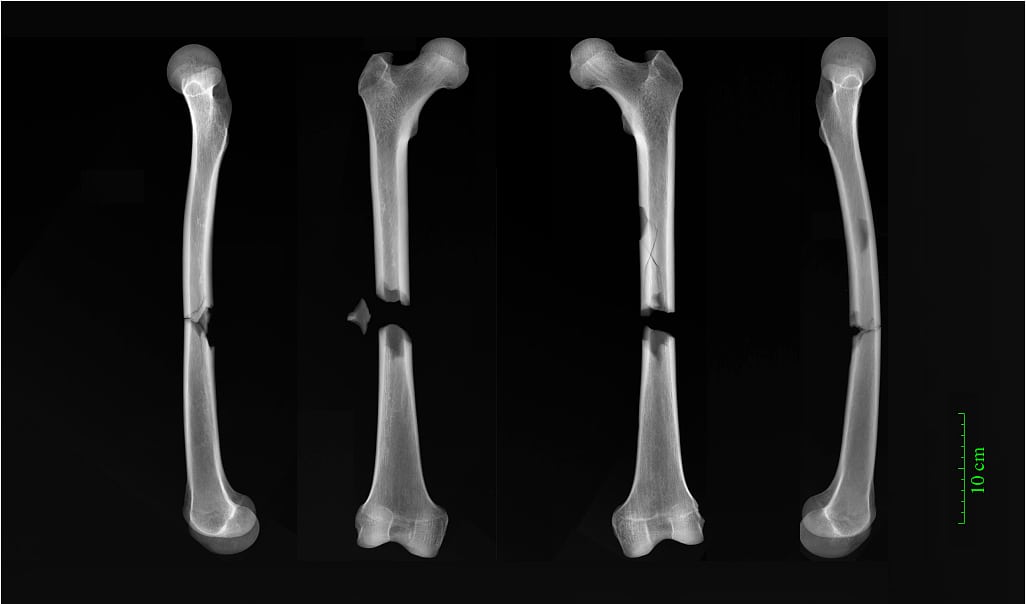

Im Fachmagazin »American Journal of Physical Anthropology« erläutern sie die Geschichte der drei Friedhöfe. In der aufstrebenden Universitätsstadt lebten damals überdurchschnittlich viele Mönche und Geistliche. Zu den zahlreichen Klöstern gehörte etwa das des Augustinerordens, in dessen Friedhof die Mönche bestattet wurden. Direkt neben ihnen fanden reiche Städter ihre letzte Ruhe, die sich für eine hohe Summe ein Grab in der geweihten Erde des Klosters geleistet hatten. An 32 Prozent der dort ausgegrabenen Individuen entdeckten die Forscher Anzeichen von mindestens einem Knochenbruch. Ein Mönch hatte zwei in der Mitte komplett durchgebrochene Oberschenkelknochen. Diese Verletzung wie auch einen Genickbruch zog er sich vielleicht bei einem tödlichen Unfall mit einem schweren Karren zu.